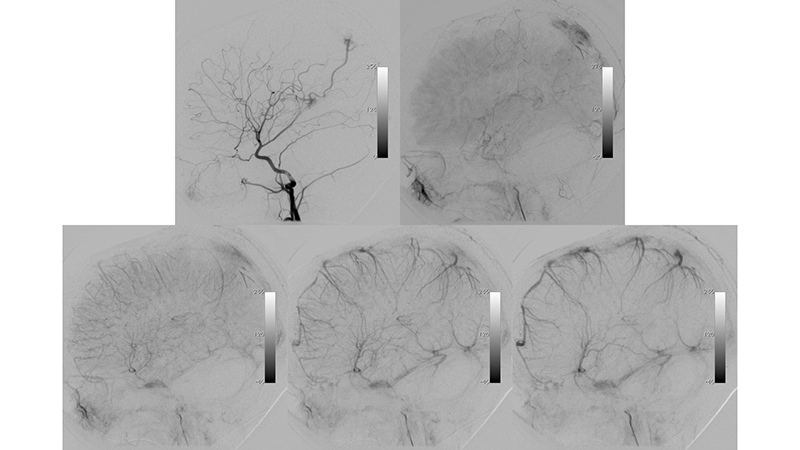

Το παιδί μετά τον πρώτο εμβολισμό παρουσίασε άμεση κλινική βελτίωση, με πλήρη αποκατάσταση της κινητικότητος του. - Προσθιοπίσθια λήψη κατά την έγχυση στην αριστερή έσω καρωτίδα ένα μήνα μετά την επέμβαση. Παρατηρείται θρόμβωση του ευθέως κόλπου και της περιοχής του Ληνού του Ηροφίλου καθώς και του τελικού τμήματος του άνω οβελιαίου κόλπου και των εγκαρσίων κόλπων. Ο μηχανισμός της θρομβώσεως, αποδίδεται στην σημαντική ελάττωση της ροής μέσα στο φλεβικό αποχετευτικό δίκτυο της φλέβας του Γαληνού και του ευθέως κόλπου που πιθανότατα οδήγησε σε φλεβική στάση και θρόμβωση.

- Πλαγία λήψη κατά την έγχυση στην αριστερή έσω καρωτίδα ένα μήνα μετά την επέμβαση. Παρατηρείται ελάχιστη άρδευση της επικοινωνίας από οπίσθιους χοριοειδείς κλάδους των οπισθίων εγκεφαλικών, καθώς και από θαλαμοδιατιτραίνοντες κλάδους που εκφύεται από το Ρ1 της αριστερής οπισθίας εγκεφαλικής αρτηρίας. Η φλεβική παροχέτευση της επικοινωνίας γίνεται προς την φλέβα του Γαληνού που είναι σημαντικά λιγότερο διατεταμένη, και δια μέσου επιπολής φλεβός της έσω επιφανείας του αριστερού βρεγματικού φλοιού προς τον αποσυμφορημένο πιά άνω οβελιαίο κόλπο. Η φλεβική αποχέτευση του ημισφαιρίου γίνεται προς το σύστημα του αριστερού σηραγγώδους κόλπου, με σημαντική αιμοδυναμική αποσυμφόρηση των ημισφαιρικών φλεβών που πλέον σκιαγραφούνται σε φυσιολογικό χρόνο.

- Προσθιοπίσθια λήψη κατά την έγχυση στην αριστερή σπονδυλική αρτηρία. Επανελέγχεται ελάχιστη υπολειμματική άρδευση της επικοινωνίας από οπίσθιους χοριοειδείς κλάδους των οπισθίων εγκεφαλικών, καθώς και από θαλαμοδιατιτραίνοντες κλάδους που εκφύεται από το Ρ1 της αριστερής οπισθίας εγκεφαλικής αρτηρίας, με θρόμβωση του ευθέως κόλπου και της περιοχής του Ληνού του Ηροφίλου καθώς και του τελικού τμήματος του άνω οβελιαίου κόλπου και των εγκαρσίων κόλπων.

- Πλαγία λήψη κατά την έγχυση στην αριστερή σπονδυλική αρτηρία. Η φλεβική παροχέτευση γίνεται προς την φλέβα του Γαληνού, και διά μέσου επιπολής φλεβός προς την έσω επιφάνεια του αριστερού βρεγματικού λοβού προς τον άνω οβελιαίο κόλπο, κατά την μετάπτωση του μέσου προς οπίσθιο τριτημόριο. Επίσης μέσω υποεπενδυματικών φλεβών που πορεύονται ενδοκοιλιακά αμφοτερόπλευρα και εκβάλλουν διά των άνω λιθοειδικών φλεβών προς το τους εγκαρσίους κόλπους, με πορεία προς τοην περιοχή του Ληνού που φαίνεται να έχει επανασηραγγοποιηθεί. Παρατηρείται αποσυμφόρηση του περιμεσεγκεφαλικού φλεβικού δικτύου με σημαντική ελάττωση της φλεβικής συμφορήσεως περιμεσεγκεφαλικά καθώς και προς τον νωτιαίο μυελό.

- Τελική αγγειογραφία επανελέγχου του σπονδυλοβασικού μετά την δεύτερη συνεδρία εμβολισμού. Παραμένουν δύο με τρεις μικροί τροφοφόροι αρτηριακοί θαλαμοδιατιτραίνοντες κλάδοι από το Ρ1 τμήμα της αριστερής οπίσθιας εγκεφαλικής αρτηρίας, που λόγω του πολύ μικρού νεγέθους των θα αντιμετωπισθούν μετά από 2 έτη. Η φλεβική παροχέτευση γίνεται προς την φλέβα του Γαληνού, και διά μέσου επιπολής φλεβός προς την έσω επιφάνεια του αριστερού βρεγματικού λοβού προς τον άνω οβελιαίο κόλπο. Οι εγκάρσιοι κόλποι και ο Ληνός έχουν επανασηραγγοποιηθεί.

- Παρατηρείται πλήρης αποσυμφόρηση του περιμεσεγκεφαλικού φλεβικού δικτύου με σημαντική ελάττωση της φλεβικής συμφορήσεως περιμεσεγκεφαλικά καθώς και προς τον νωτιαίο μυελό.